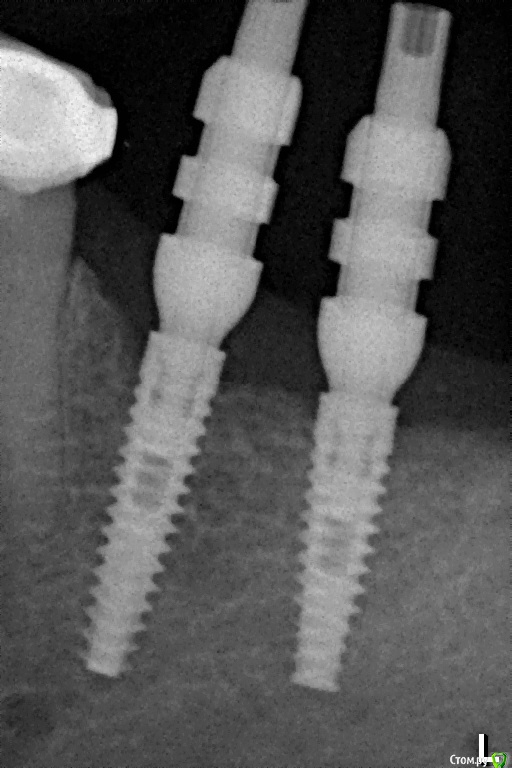

Pavel-Pskov Опубликовано 24 мая, 2016 Поделиться Опубликовано 24 мая, 2016 В момент снятия слепков май 2014 г.Неделя назад Ссылка на комментарий